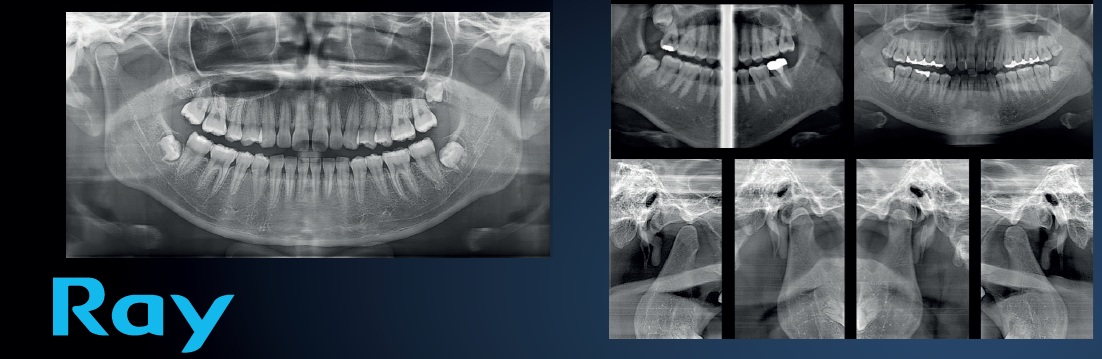

Ontdek de kracht van geavanceerde 3D-beeldvorming met de RAYSCAN Alpha Plus 160. Deze alles-in-één oplossing combineert CBCT-scans, panoramische röntgenbeelden en cephalometrie in één compact en gebruiksvriendelijk toestel. Dankzij een uitzonderlijke beeldkwaliteit tot 70 µm, een variabel beeldveld tot 16 × 10 cm en een lage stralingsdosis, ondersteunt RAYSCAN u bij elke stap van uw klinische workflow – van diagnose tot behandelplanning.

Of het nu gaat om implantologie, orthodontie, endodontie of kaakchirurgie, RAYSCAN Alpha Plus 160 levert snel en betrouwbaar de informatie die u nodig heeft. Met zijn intuïtieve bediening, snelle scantijd en geavanceerde softwaretools tilt dit toestel uw praktijk naar een hoger niveau van precisie, efficiëntie en patiëntenzorg.

Panoramisch met automatische autofocus

Met de Adaptive Moving Focus-technologie worden automatisch de beste beeldlagen geselecteerd voor duidelijke en nauwkeurige panoramische opnames. Dit maakt het eenvoudig om de parodontale toestand van uw patiënt te evalueren en laesies precies te lokaliseren.